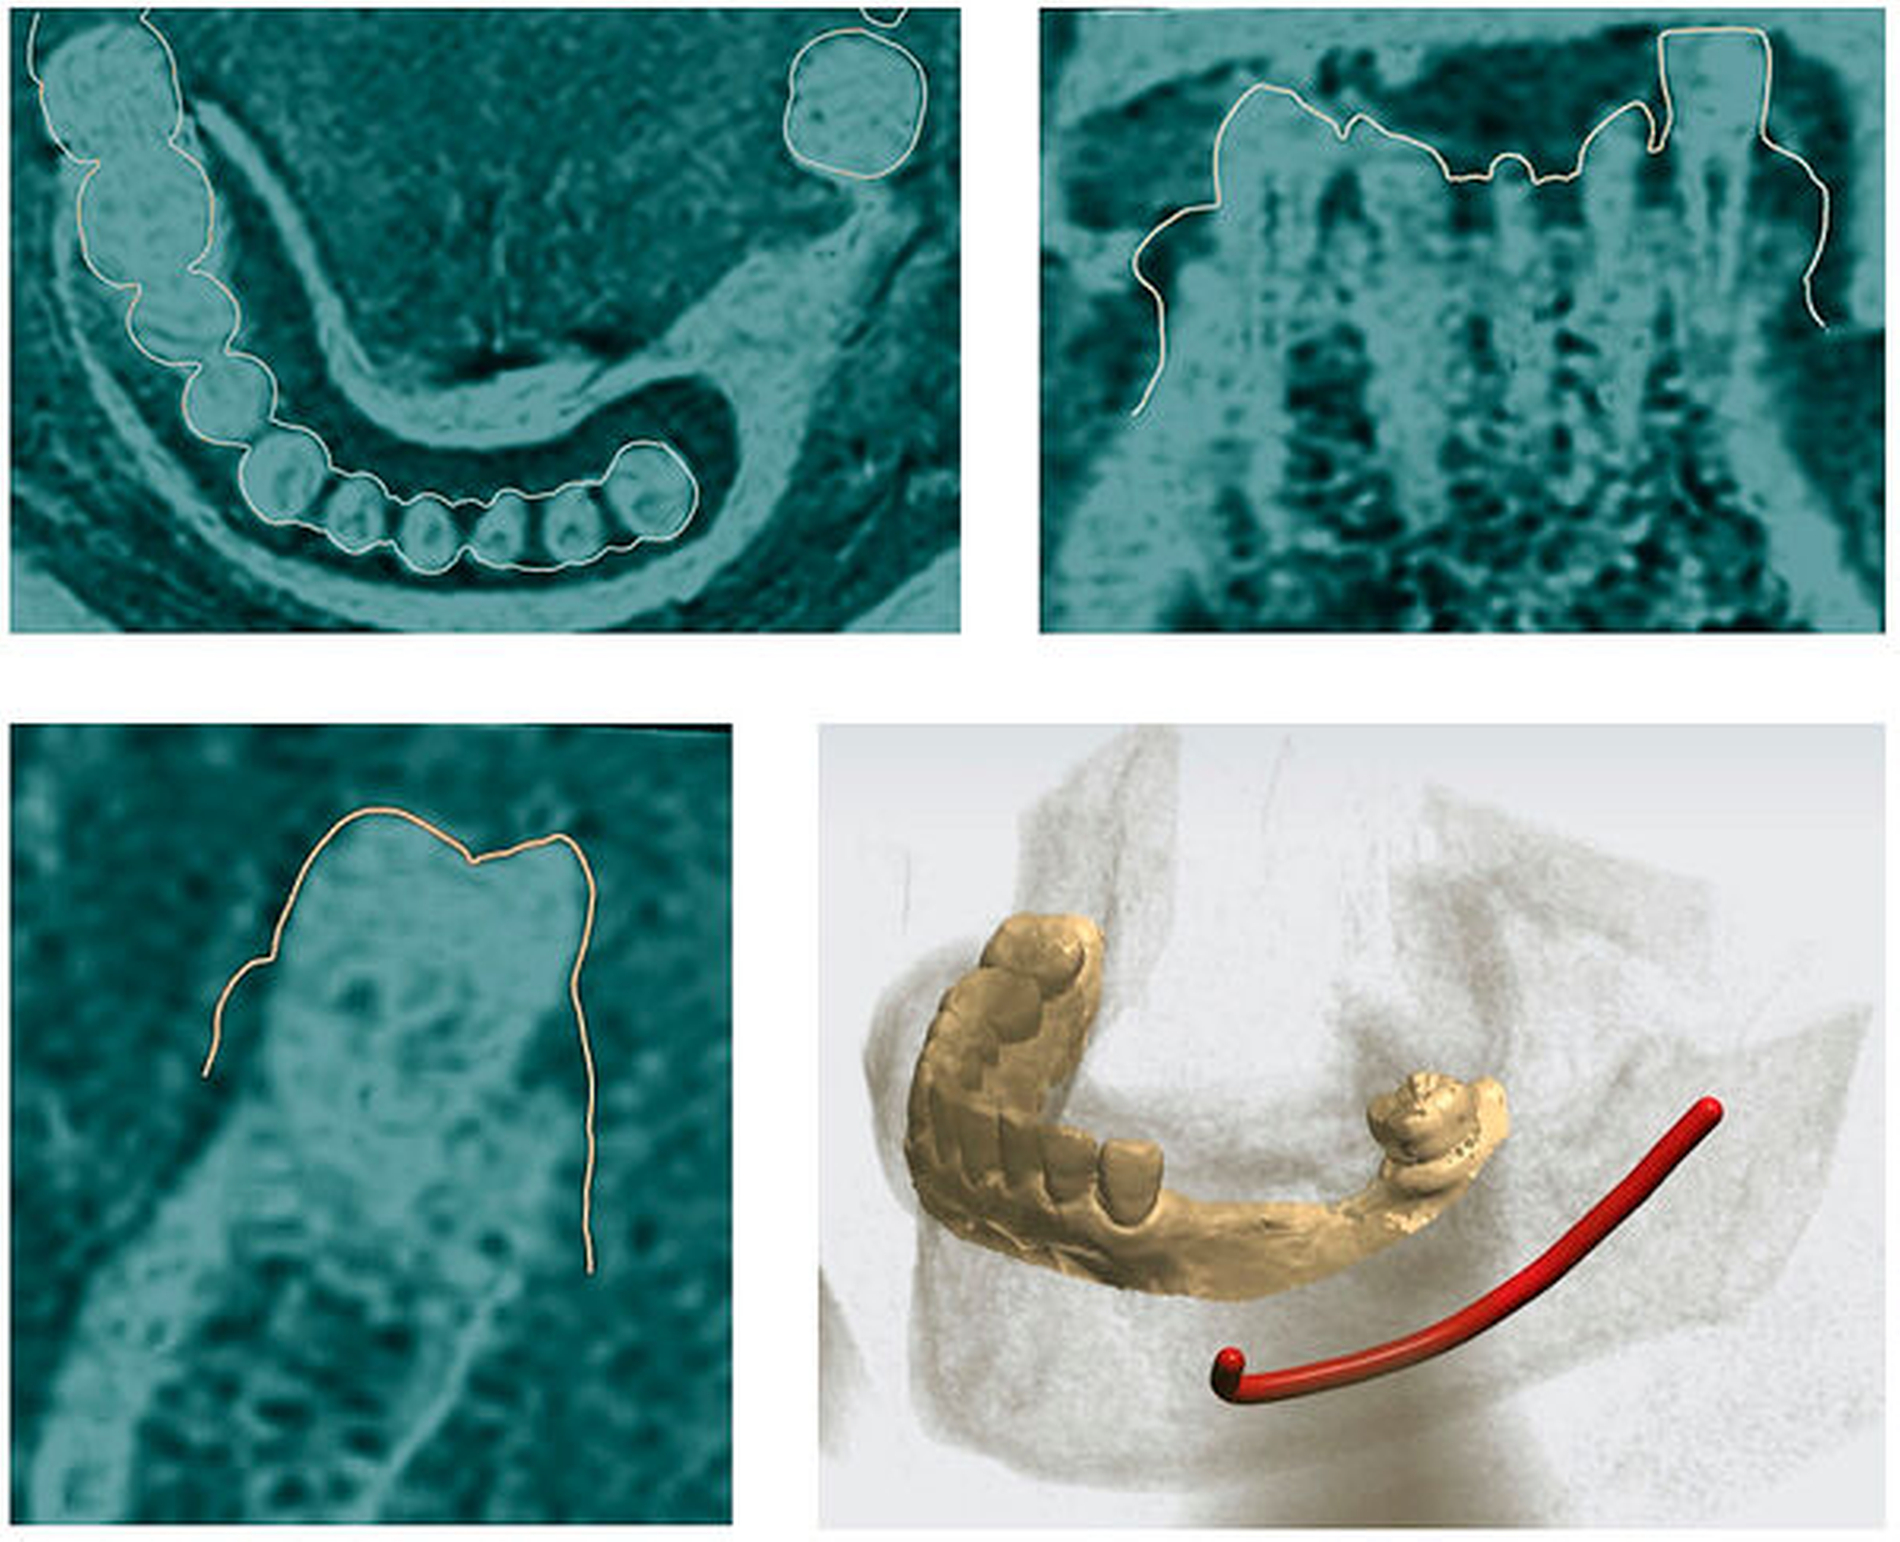

Bei der MRT-Untersuchung werden – wie bei CT oder DVT – Daten im DICOM-Format bereitgestellt und können in gängige Implantatprogramme wie coDiagnostiX® (Dental Wings) oder Implant Studio® (3Shape) importiert werden. Analog zur DVT-Planung werden zusätzlich hochauflösende Datensätze der Zahnoberflächen im STL-Format importiert, die direkt über Intraoralscans oder indirekt mittels Modellscan akquiriert wurden. Die MRT-Daten werden anschließend mit dem Oberflächenscan der Zähne koregistriert. Dabei wird die Ausrichtung des Oberflächenscans in der koronalen, der axialen und der sagittalen Ebene mithilfe von Translations- und Rotationswerkzeugen optimiert. Das Ergebnis ist ein „Hybrid-Modell“, bestehend aus einem hochpräzisen Scan der Zahnoberflächen und der MRT (Abbildung 2).

Anschließend kann die Implantatpositionierung entsprechend den prothetischen Anforderungen, dem sogenannten „Backward Planning“, und unter Berücksichtigung der anatomischen Situation festgelegt werden (Abbildung 3). In der Seitenzahnregion des Unterkiefers kann im Gegensatz zur DVT der Verlauf des Nerven-Gefäßbündels (Nervus alveolaris inferior) eindeutig und direkt visualisiert werden [Probst et al., 2017; Burian et al., 2019; Probst et al., 2020], was einen gewissen Sicherheitsaspekt beinhaltet [Agbaje et al., 2017] (Abbildung 4).